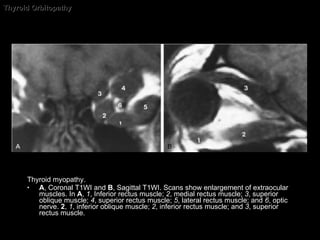

Thyroid Orbitopathy Pathology: Infiltration by mast cells and lymphocytes, edema, muscle fiber necrosis, lipomatosis, fatty degeneration. The inferior rectus muscle is involved most commonly , followed by the medial rectus and the superior rectus.

Thyroid Orbitopathy Pathology: Infiltration by mast cells and lymphocytes, edema, muscle fiber necrosis, lipomatosis, fatty degeneration. The inferior rectus muscle is involved most commonly , followed by the medial rectus and the superior rectus. mnemonic:  I ' M   S L ow  I nferior M edial S uperior L ateral

Thyroid Orbitopathy CT and MR imaging: Coke-bottle sign  : Enlarged muscle belly with  sparing  the anterior tendinous insertion.  Low-density on CT: acc of lymphocytes and mucopolysaccharide deposition. HyperSI T2WI within muscle: represent inflammation, good clinical response to a trial of steroid therapy. Increased orbital fat Enlargement of the lacrimal glands Edema eyelids Proptosis. Stretching optic n.

Thyroid Orbitopathy Thyroid myopathy. Axial CT scan shows enlargement of the inferior rectus muscles ( arrows ).

Thyroid Orbitopathy Thyroid myopathy.  A , Coronal T1WI and  B , Sagittal T1WI. Scans show enlargement of extraocular muscles. In  A ,  1 , Inferior rectus muscle;  2 , medial rectus muscle;  3 , superior oblique muscle;  4 , superior rectus muscle;  5 , lateral rectus muscle; and  6 , optic nerve.  2 ,  1 , inferior oblique muscle;  2 , inferior rectus muscle; and  3 , superior rectus muscle.